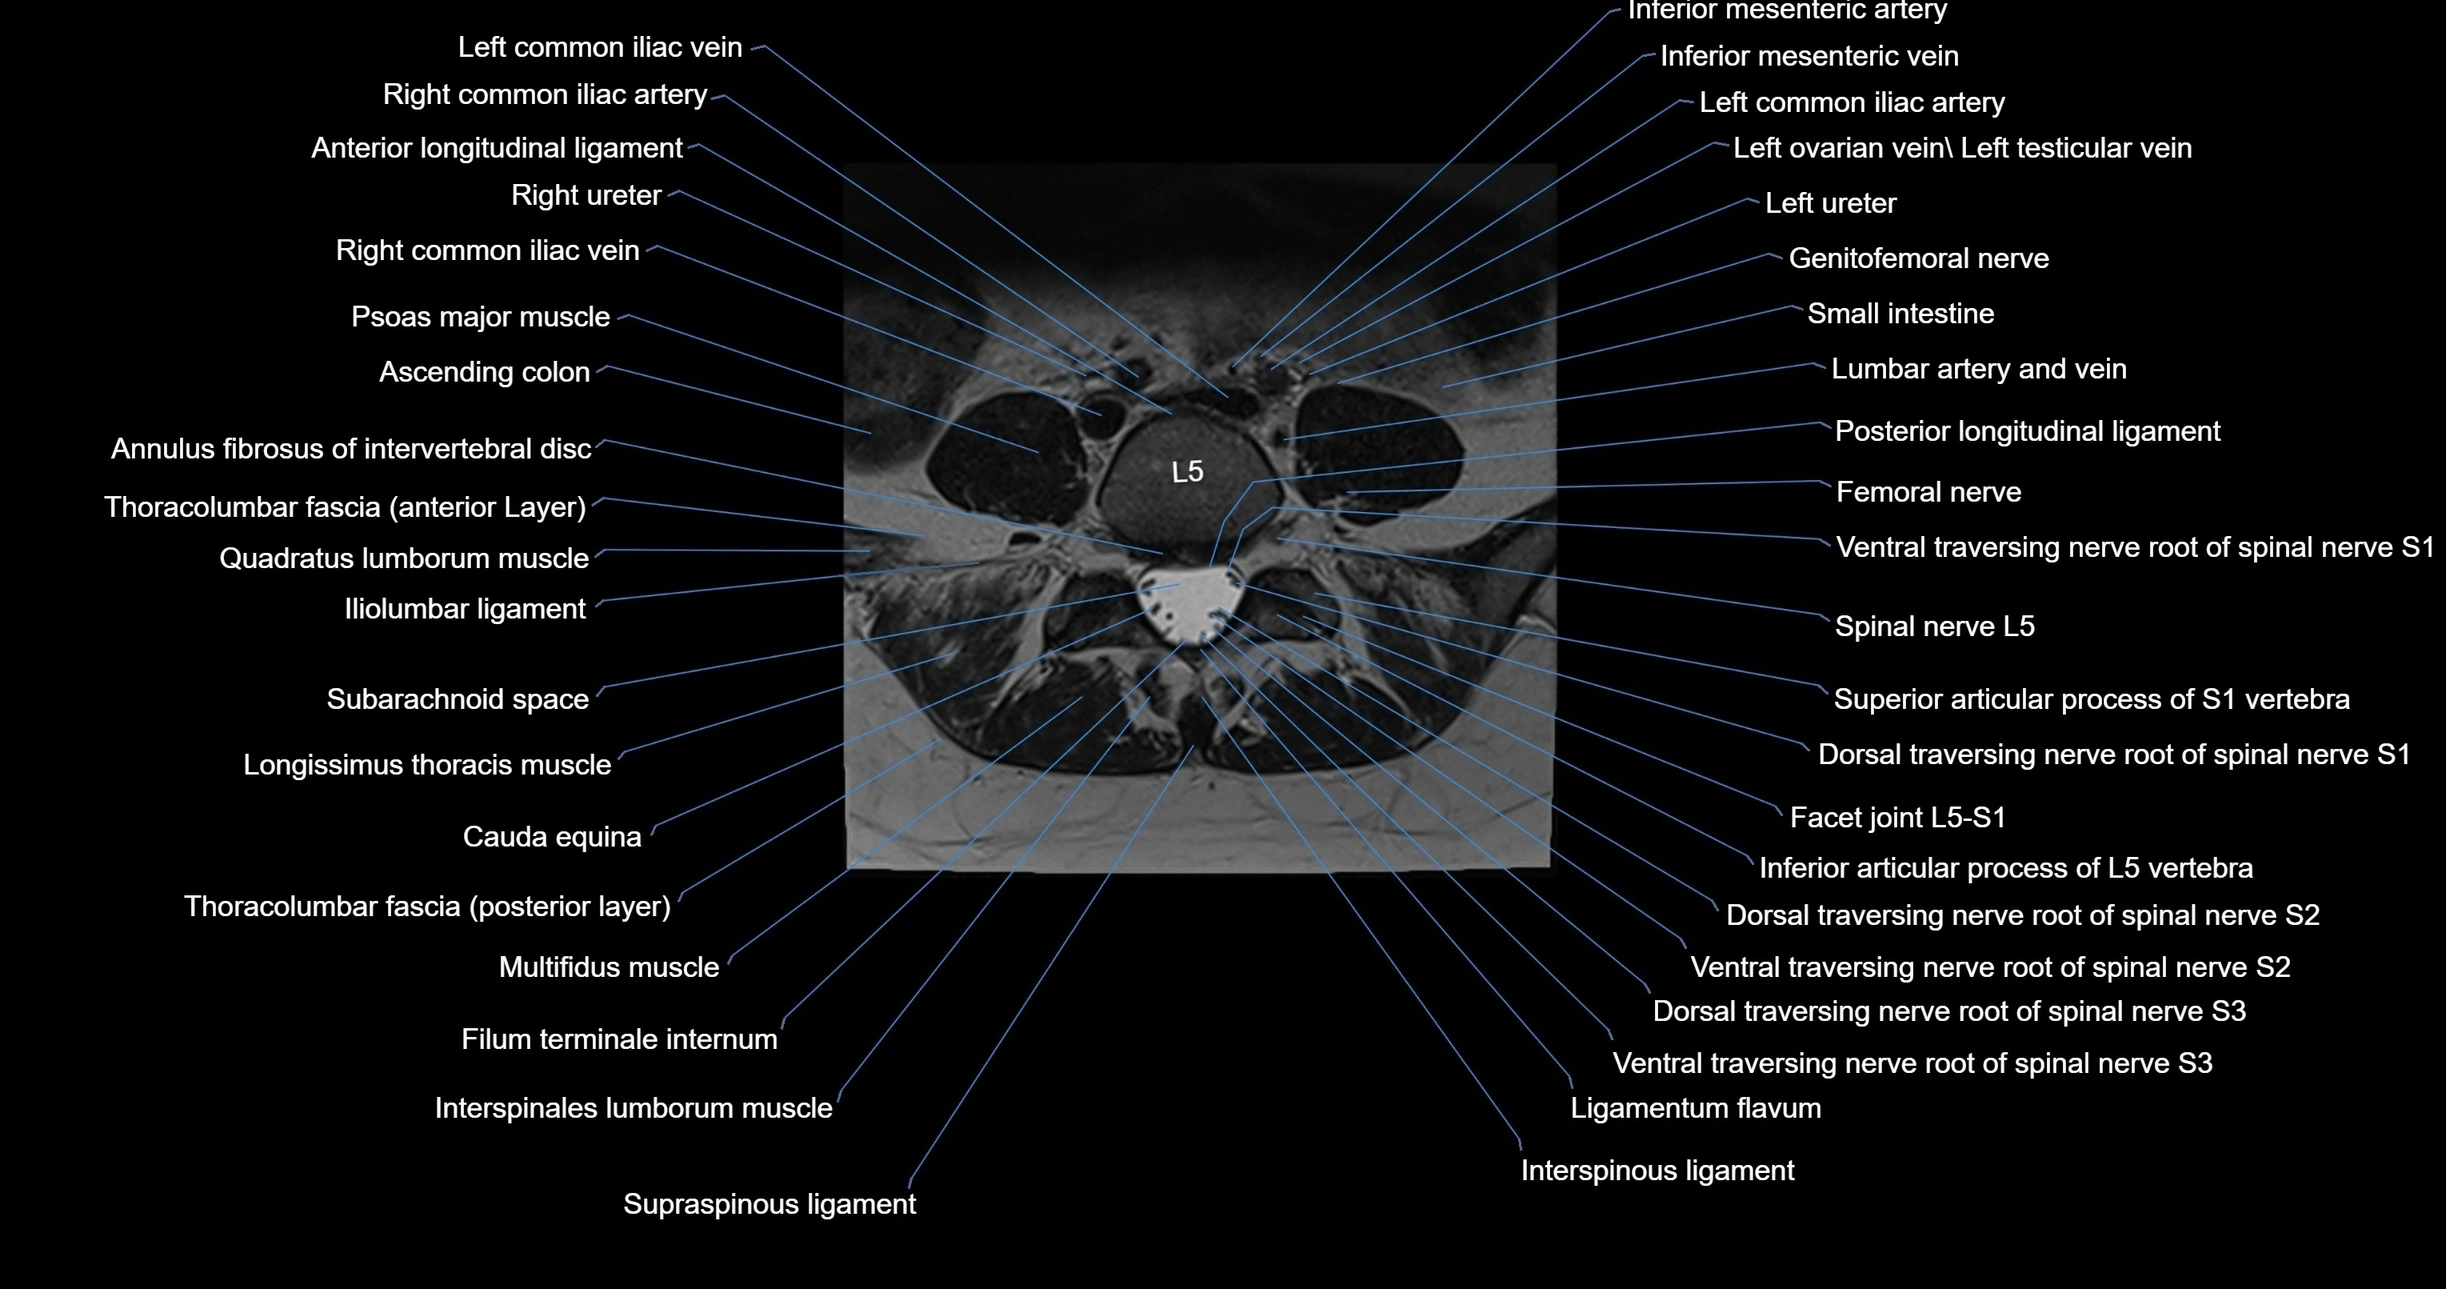

MRI images